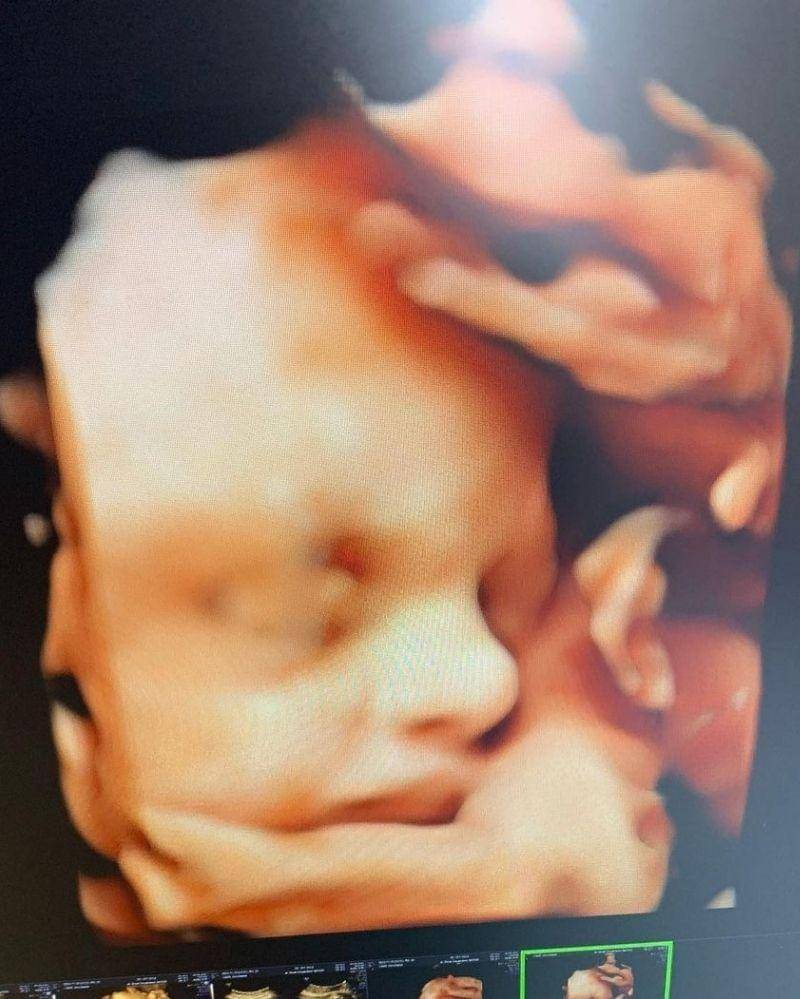

15. Ardashir Behrouz Al Barraq, putra Angbeen Rishi dan Adly Fayruz

Pasangan Adly Fairuz dan Angbeen Rishi melahirkan anak pertama mereka yang berjenis kelamin laki-laki pada 1 Januari 2021. Pasangan ini memberikan nama indah, yaitu Ardashir Behrouz Al Barraq.

Saat mengandung Ardashir, Angbeen Rishi juga sempat membagikan cuplikan video hasil USG baby Ardashir. Dari unggahan tersebut, banyak warganet yang terpesona dengan hidung mancung Ardashir.